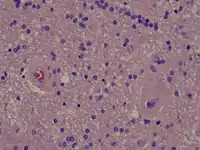

Radiation necrosis

- Brain Radiation Necrosis

Low power microscopy

Intermediate power microscopy

High power microscopy